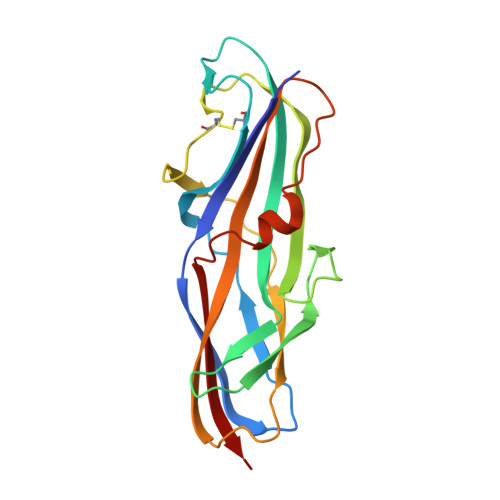

Carbohydrate-Lectin Interactions: An Unexpected Contribution to Affinity.

Navarra, G., Zihlmann, P., Jakob, R.P., Stangier, K., Preston, R.C., Rabbani, S., Smiesko, M., Wagner, B., Maier, T., Ernst, B.(2017) Chembiochem 18: 539-544

4Z3E, 4Z3F, 4Z3G, 4Z3H, 4Z3I, 4Z3J - PubMed Abstract:

Uropathogenic E. coli exploit PapG-II adhesin for infecting host cells of the kidney; the expression of PapG-II at the tip of bacterial pili correlates with the onset of pyelonephritis in humans, a potentially life-threatening condition. It was envisaged that blocking PapG-II (and thus bacterial adhesion) would provide a viable therapeutic alternative to conventional antibiotic treatment. In our search for potent PapG-II antagonists, we observed an increase in affinity when tetrasaccharide 1, the natural ligand of PapG-II in human kidneys, was elongated to hexasaccharide 2, even though the additional Siaα(2-3)Gal extension is not in direct contact with the lectin. ITC studies suggest that the increased affinity results from partial desolvation of nonbinding regions of the hexasaccharide; this is ultimately responsible for perturbation of the outer hydration layers. Our results are in agreement with previous observations and suggest a general mechanism for modulating carbohydrate-protein interactions based on nonbinding regions of the ligand.